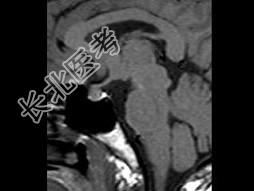

- 单项选择题女,25岁, 双侧泌乳,月经不调半年, 服药效果不佳,根据所提供图像, 最可能的诊断是 ( )

E、垂体微腺瘤